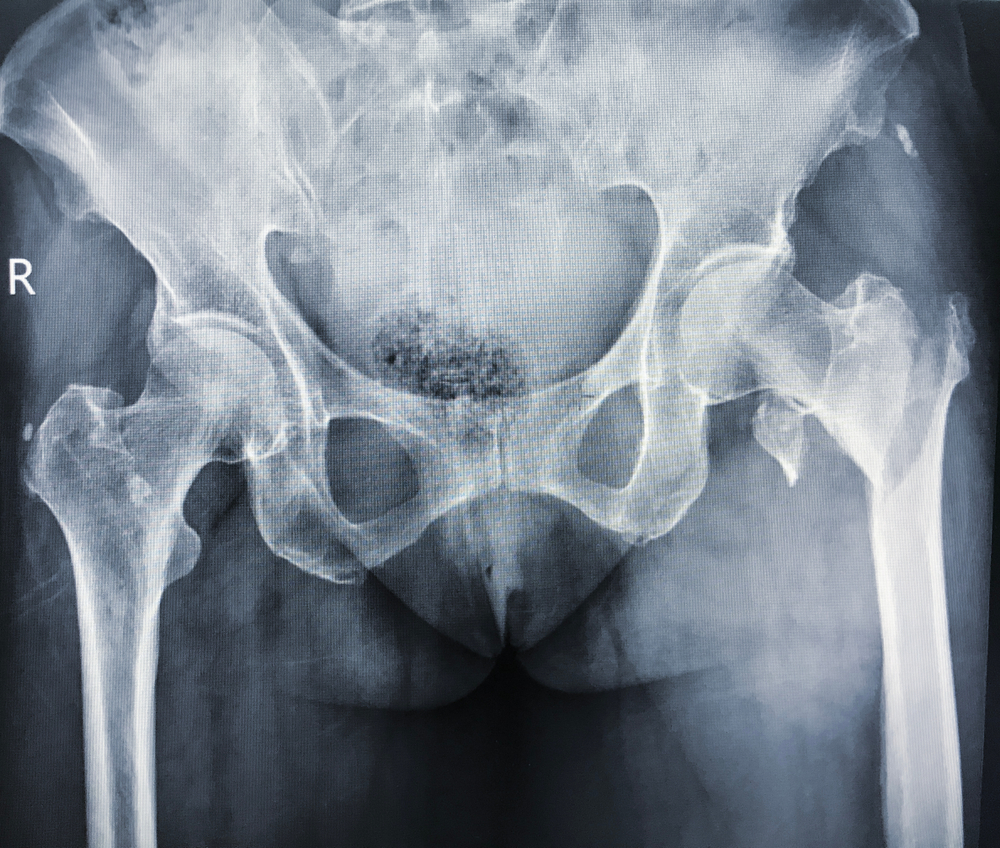

Поставить точный диагноз «вертельный перелом бедра» помогает рентгенологическое исследование. Оно должно проводиться всем пациентам после типичного механизма травмы с болью в паху или в области большого вертела, которая нарастает при осевой нагрузке на ногу. При переломах со смещением для визуализации перелома достаточно выполнить обычную рентгенографию в прямой и боковой проекции. Определенные сложности с интерпретацией результатов могут возникать при вколоченных переломах. В таких случаях исследование выполняется в положении приведения и отведения ноги. Если данных рентгенографии недостаточно, то больному назначается компьютерная томография.